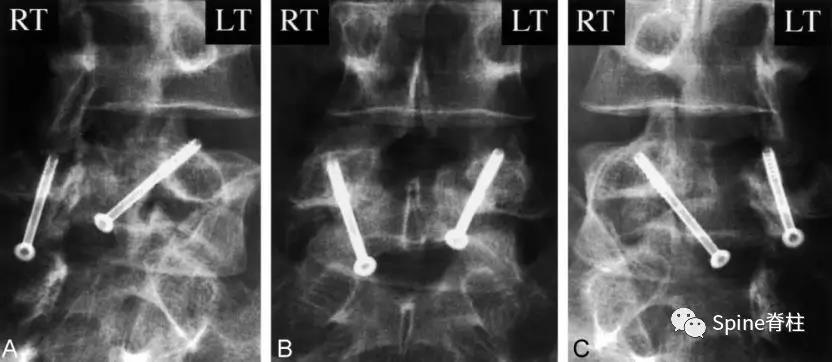

图:6个月复查可见右侧椎弓根裂已愈合(单箭头),但出现右侧峡部裂(双箭头)